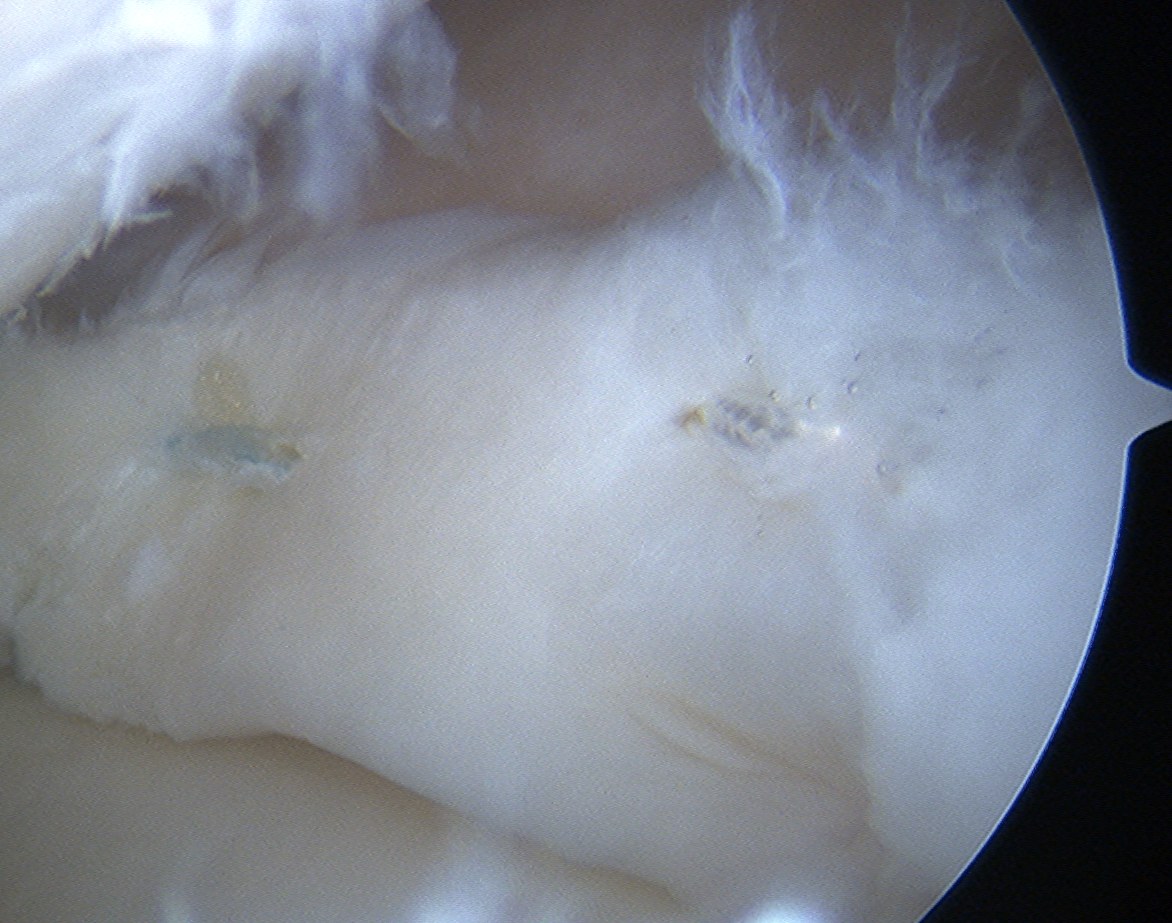

4. Meniscal Root Repair

Definition

- tear of insertion of posterior horn of meniscus

- difficult to fix

- must repair down to bone

Technique

- ACL guide

- drill hole up into mensical root insertion

- use suture passer to secure meniscal root

- retrieve sutures down through bone tunnel in tibia

- tie over screw post